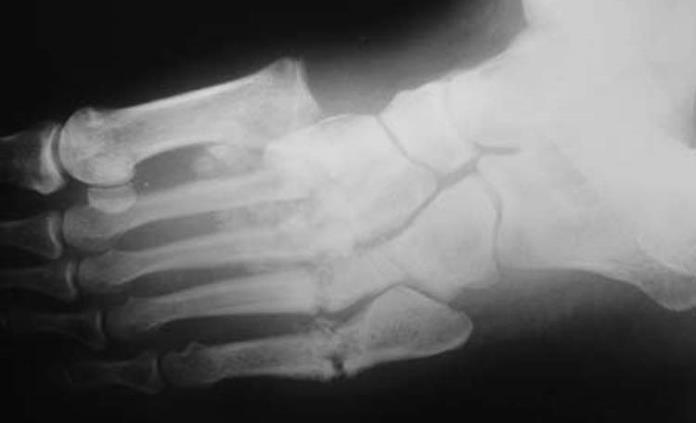

Para confirmar el padecimiento los médicos pueden utilizar una radiografía para detectar la presencia de una posible lesión articular, también pueden ayudarse de la ecografía y la gammagrafía. Además entre más pronto se detecte la enfermedad, los médicos podrán cambiar el curso de la enfermedad.